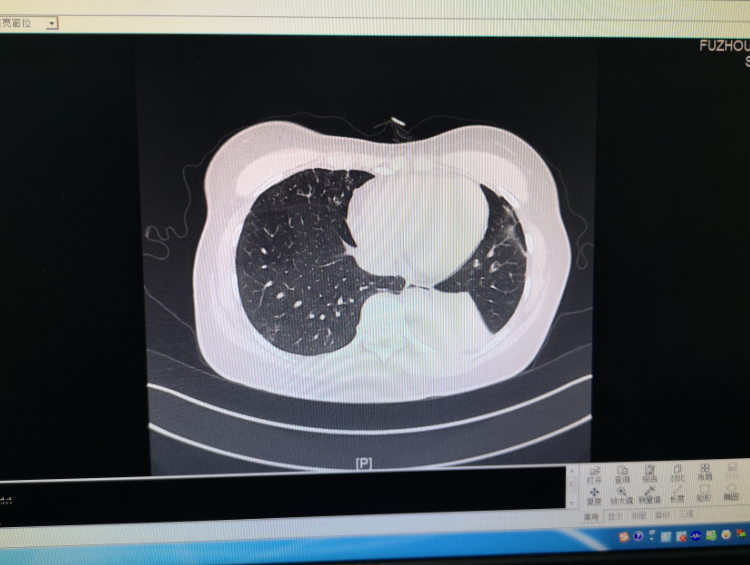

小明的肺炎康复之旅,最新真实体验分享

摘要:关于肺炎的最新真实情况,小明的肺炎康复之旅展现了他惊人的恢复力。经过一系列治疗,小明开始逐步康复,他的经历鼓舞了许多人。这段旅程充满了挑战和奇迹,最终小明成功战胜病魔,重新获得健康。故事开始于一个普通的早晨,小...